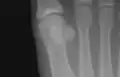

![]() The first metatarsal. (Left.) | |

The first metatarsal bone is the bone in the foot just behind the big toe. The first metatarsal bone is the shortest of the metatarsal bones and by far the thickest and strongest of them.[1]

Like the four other metatarsals, it can be divided into three parts: base, body and head. The base is the part closest to the ankle and the head is closest to the big toe. The narrowed part in the middle is referred to as the body of the bone. The bone is somewhat flattened, giving it two sides: the plantar (towards the sole of the foot) and the dorsal side (the area facing upwards while standing).[1]